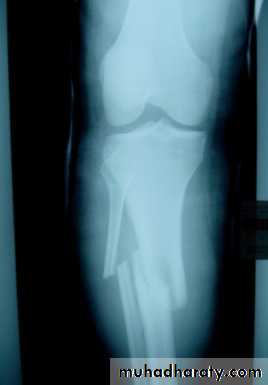

Fractures shaft tibia and fibula

Most fractures in this region involve both the tibia and the fibula. Fractures of the shafts of the tibia and fibula may occur either from an angulatory force or rotational force , Road traffic accident and motorcycle accident are the common cause.Twisting force cause spiral fracture of both bones at different level, while Direct injury crushes the skin and fractures both bone at the same level.

X-ray shows the type and severity of displacement.